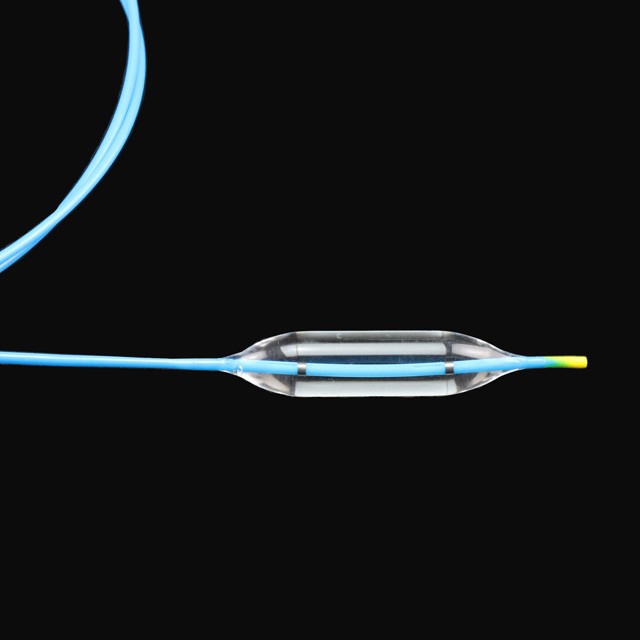

●Ballónin kann stigalast økjast við trimum ymiskum diametrum undir serligum trýsti, geva nógv meira val til læknar{0}}

●Rapid drenagusniðgeving hjálpir til at minka um skurðviðgerðartíðina{0}}

●Optimal sniðgeving av rørinum ger tað slætt og av góðari elastisiteti,sterk snúningsmótstøða og lættari gjøgnumgongdir{0}}

● Radiopaque-markørarnir á báðum endunum á ballónini kunnu geva nágreiniliga staðseting undir røntgen{1}}